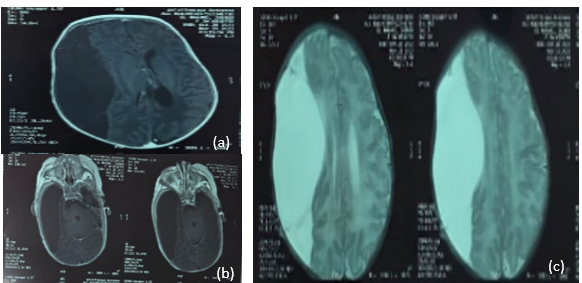

Cranial ultrasound, CT (Figure 1), and MRI (Figure 2) demonstrated a large right fronto-temporo-parietal extra-axial cystic lesion with significant mass effect and midline shift. Laboratory results were normal.

Figure 2: Axial MRI demonstrating a right fronto-temporo-parietal extra-axial lesion. The lesion appears hypointense on non-contrast T1-weighted images (A), does not enhance after contrast administration on T1-weighted images, and is hyperintense on T2-weighted images, with no evidence of hemorrhage.